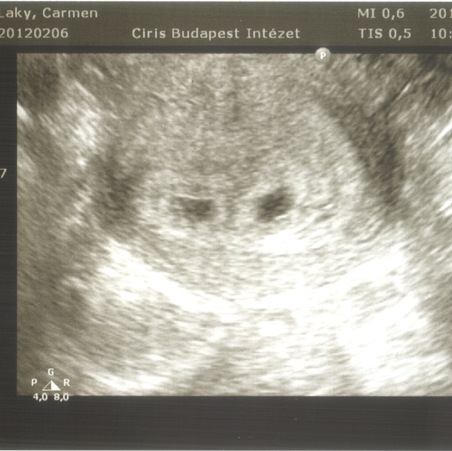

Beszkenneltem az UH képeket:) nem tudom, mennyi fog belőle látszani.

Kép

Kép [/img]

Süti, tök jó a két pöttyös kép, tényleg olyan, mint egy UHU :)

Gyönyörűek a pöttyeid! Örülök, hogy minden oké!